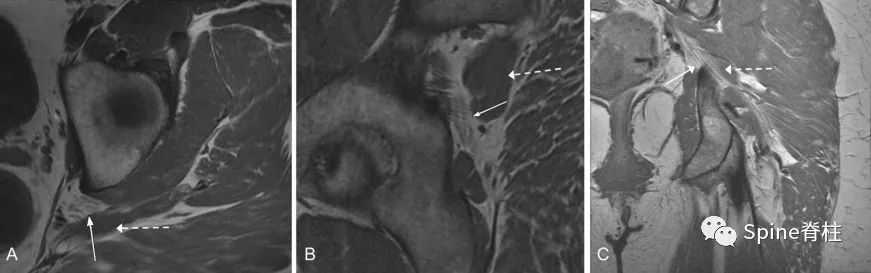

图示:MRI T1像的 Beaton-Anson 1型 ( 最常见的坐骨神经解剖,被认为是正常型 )。坐骨神经的胫神经与腓总神经部分(细箭头)位于梨状肌(虚箭头)的前面。轴位(A)、矢状位(B)和冠状位(C)平面。